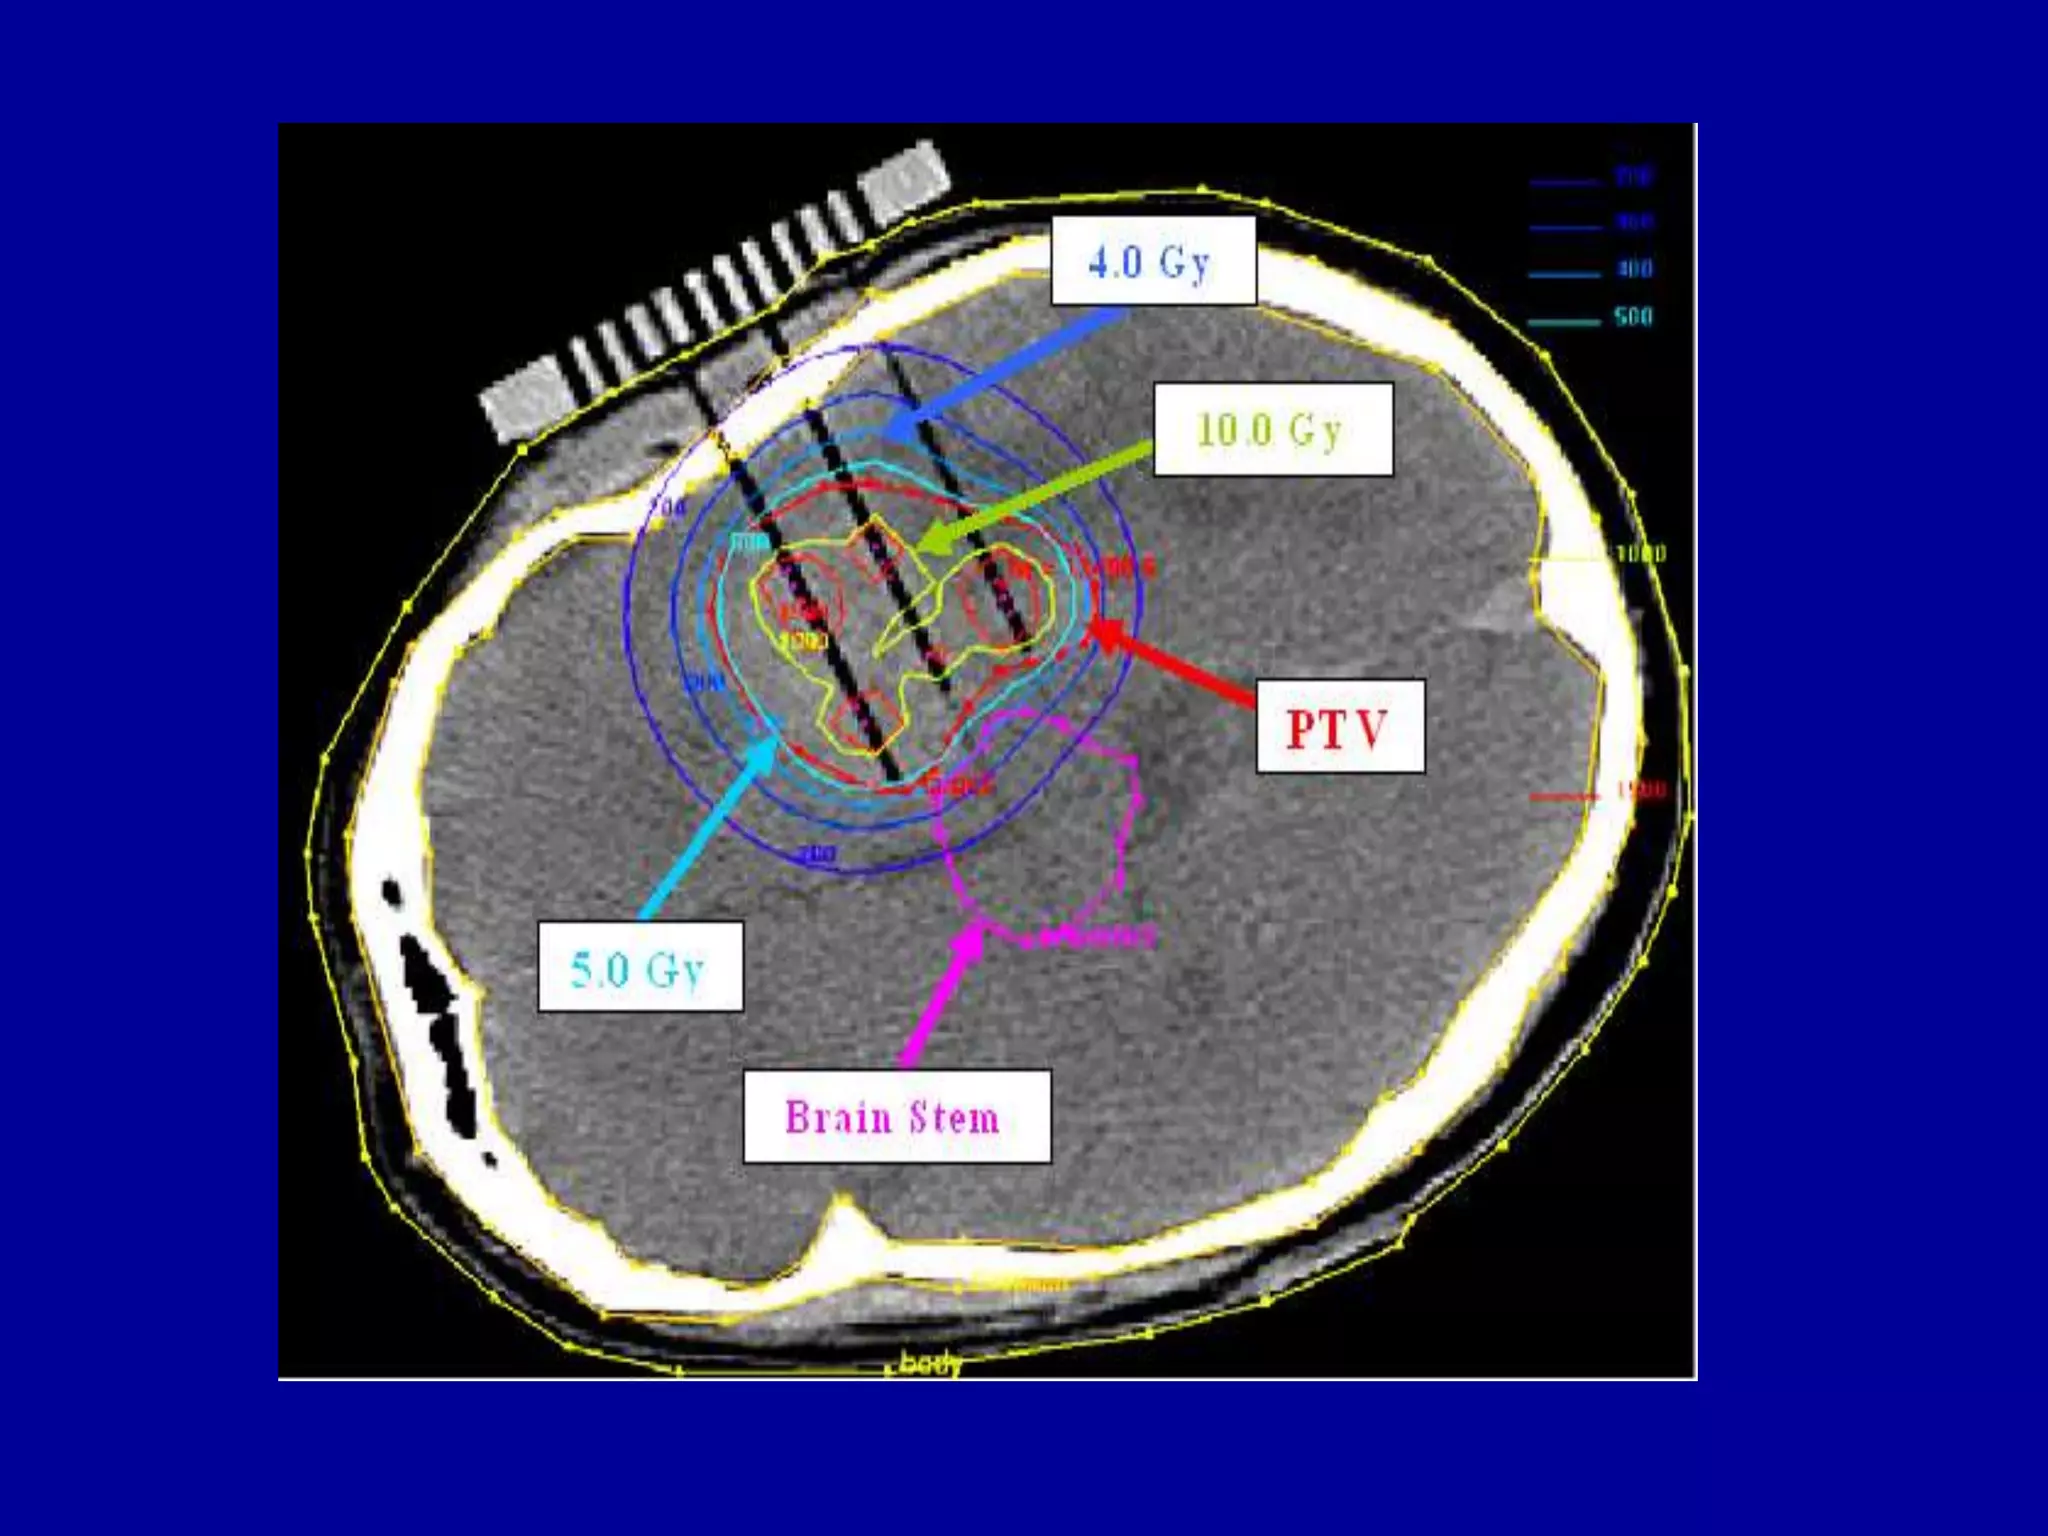

Gliasite Brachytherapy